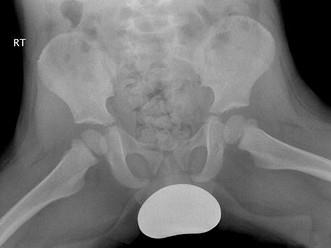

男,请根据其正常骨盆影像图像,判断其最可能的年龄 ( )A、11岁左右B、14岁左右C、5岁左右D、8岁左右E、2岁左右

问题 男,请根据其正常骨盆影像图像,判断其最可能的年龄 ( )

选项 A、11岁左右 B、14岁左右 C、5岁左右 D、8岁左右 E、2岁左右

答案 E